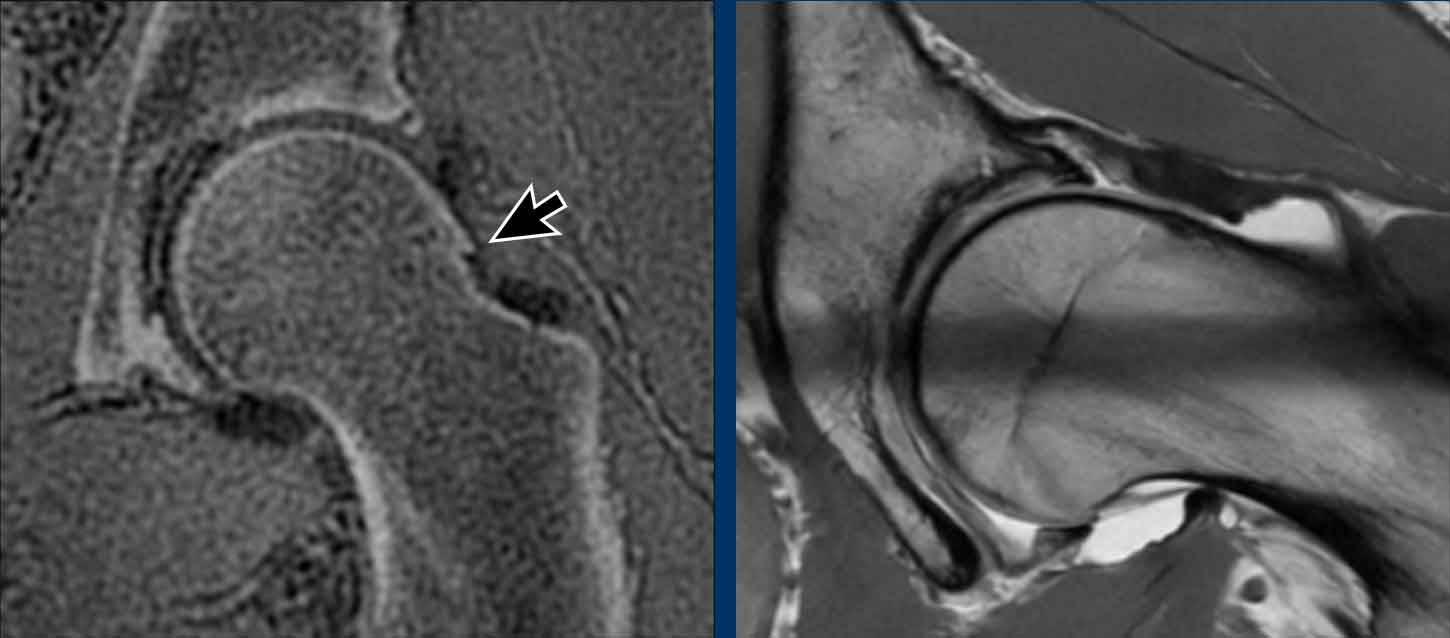

Đây là nam bệnh nhân 27 tuổi, xuất hiện đau sâu vùng bẹn phía trước cách đây bảy năm khi đang ngồi xổm.

Kể từ đó, bệnh nhân đã ngừng chơi bóng đá nhưng vẫn tiếp tục bị đau.

Hình ảnh

Các phim X-quang cho thấy một gờ xương nhô ra ở đầu/cổ xương đùi phù hợp với hình thái cam.

Continue with the MRI…

Hình ảnh bên trái là MRI xương/thời gian echo bằng không (ZTE).

Đây là một kỹ thuật chụp MRI đặc biệt để khảo sát xương.

Các hình ảnh trông khá giống với hình ảnh CT và có thể được thực hiện như một phần của chụp MRI-arthrogram khớp háng.

Hình ảnh cho thấy một gai xương nhỏ (mũi tên đen).

Cuộn qua các hình ảnh của MRI-arthrogram ở phía bên phải.

Có một tổn thương sụn ở phía ổ cối (mũi tên vàng).